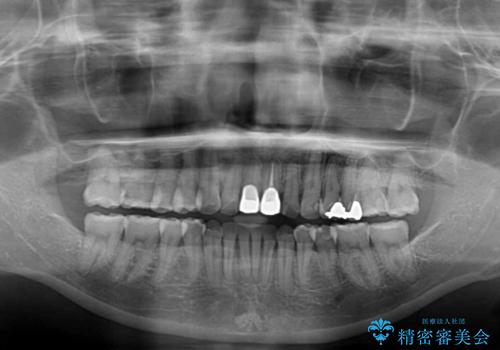

- 前歯のデコボコと変色した前歯を気にして来院された患者様です。

抜歯矯正により口元を引っ込めることも検討しましたが、特に口元の突出感は気になっていないとのことで、非抜歯にてワイヤー装置で矯正治療を行うこととしました。

気になっていた前歯の変色も、矯正治療後にオールセラミッククラウンにて補綴治療を行うこととしました。

舌の突出癖により治療期間中に開咬となり、治療が長引きましたが、口元も治療前よりも引っ込めることができ、すっきりとした仕上がりとなりました。